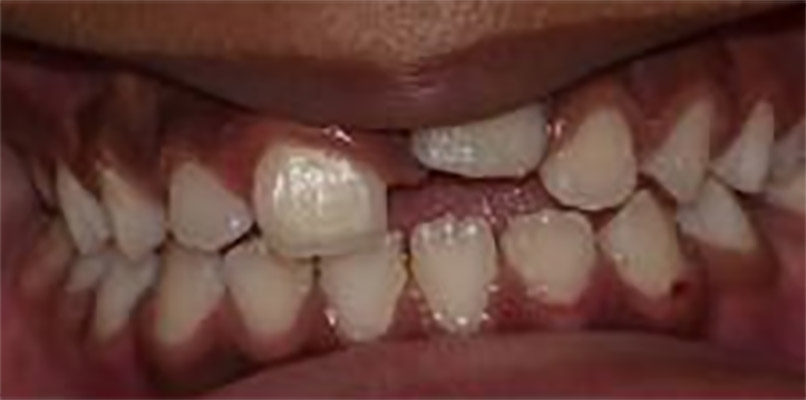

- Non-erupted tooth #8 and missing tooth #T

- Partially Erupted Teeth #6 and #11.

Cavitated lesions on teeth:#3-O #A-OBL,#14-O #19-O,#L-O, #S-O,and #30-OB

Figures 4,5 & 6: Posterior right, anteriors, and posterior left